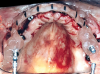

Fig 15. Maxillary arch with final prosthesis.

Figure 15

The implant-supported, screw-retained, hybrid acrylic complete denture in the maxilla and the mandibular implant fixed prostheses were delivered after torquing the custom abutments to 32 Ncm and the octa abutments to 35 Ncm, and metal frames, including the interlocks, were tried-in. After consensus was obtained on the phonetics, occlusion, and esthetics (Figure 15), the fit was verified by periapical radiographs. The patient, who was very satisfied with the result, was instructed in proper oral hygiene.